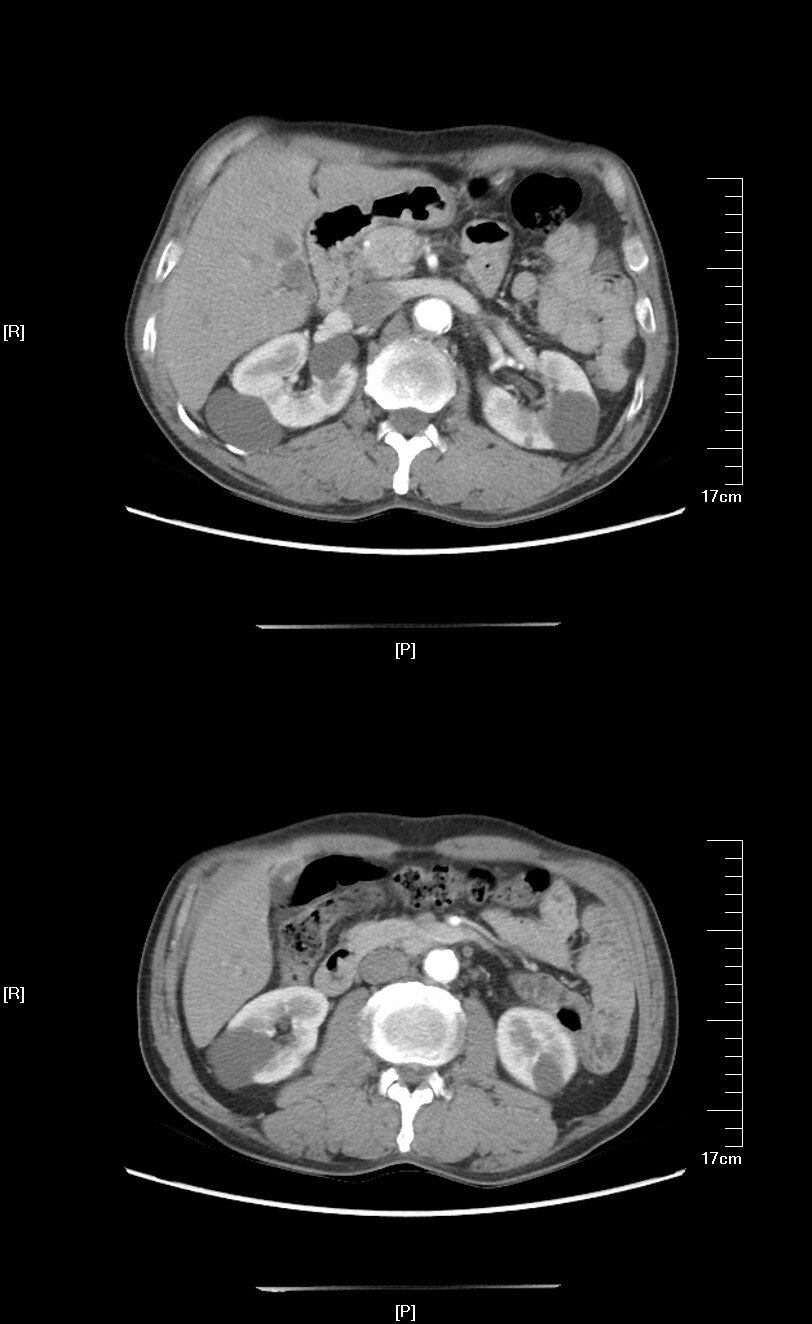

肾盂旁囊肿

肾盂旁囊肿,肾盂囊肿

囊肿位于肾实质内,与肾盂邻近,确诊肾盂旁囊肿

2020年08月手术患者:双肾多发囊肿,右肾存在肾窦内动脉旁的肾盂旁囊肿